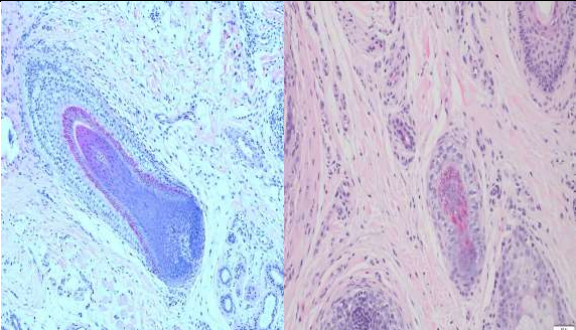

A 39-year-old male presented to the dermatology clinic of a Veterans Affairs medical center with a cystic nodule of the left medial eyebrow measuring 0.8 x 0.7 cm (figure 1). The patient was known to have CCS. His father, paternal aunt, and paternal grandfather had been diagnosed with Brooke-Spiegler syndrome (diagram 1). After presenting with multiple trichoepitheliomas, he had tested positive for a heterozygous pathogenic variant (c.2288-2289del p.Phe 763) of CYLD NM-015247.2CYLD. With this history, the clinical differential for this eyebrow lesion was cylindroma versus spiradenoma. Microscopic examination of the excision specimen revealed a well-circumscribed, dermal-based adnexal proliferation with areas recapitulating each part of the normal hair follicle: the?infundibulum, inner root sheath, outer root sheath, matrix, and bulb (figure 2.A&B). Areas resembling the infundibular portion of the hair follicle contained cystic cell aggregates lined by stratified squamous epithelium with a granular layer and filled with “basket-weave” orthokeratin (figure 2.C). Areas resembling the suprabulbar portion of the hair follicle showed clear cells as seen in the external root sheath and eosinophilic cells as seen in the internal root sheath (figure 2.D&E). Areas resembling the bulbar portion of the hair follicle showed immature basaloid cells and papillary mesenchymal bodies (figure 2.F&G). The lesion was uniformly circumscribed and without cytologic atypia, so a diagnosis of PF was rendered.

Figure 1,2,3

Figure 2